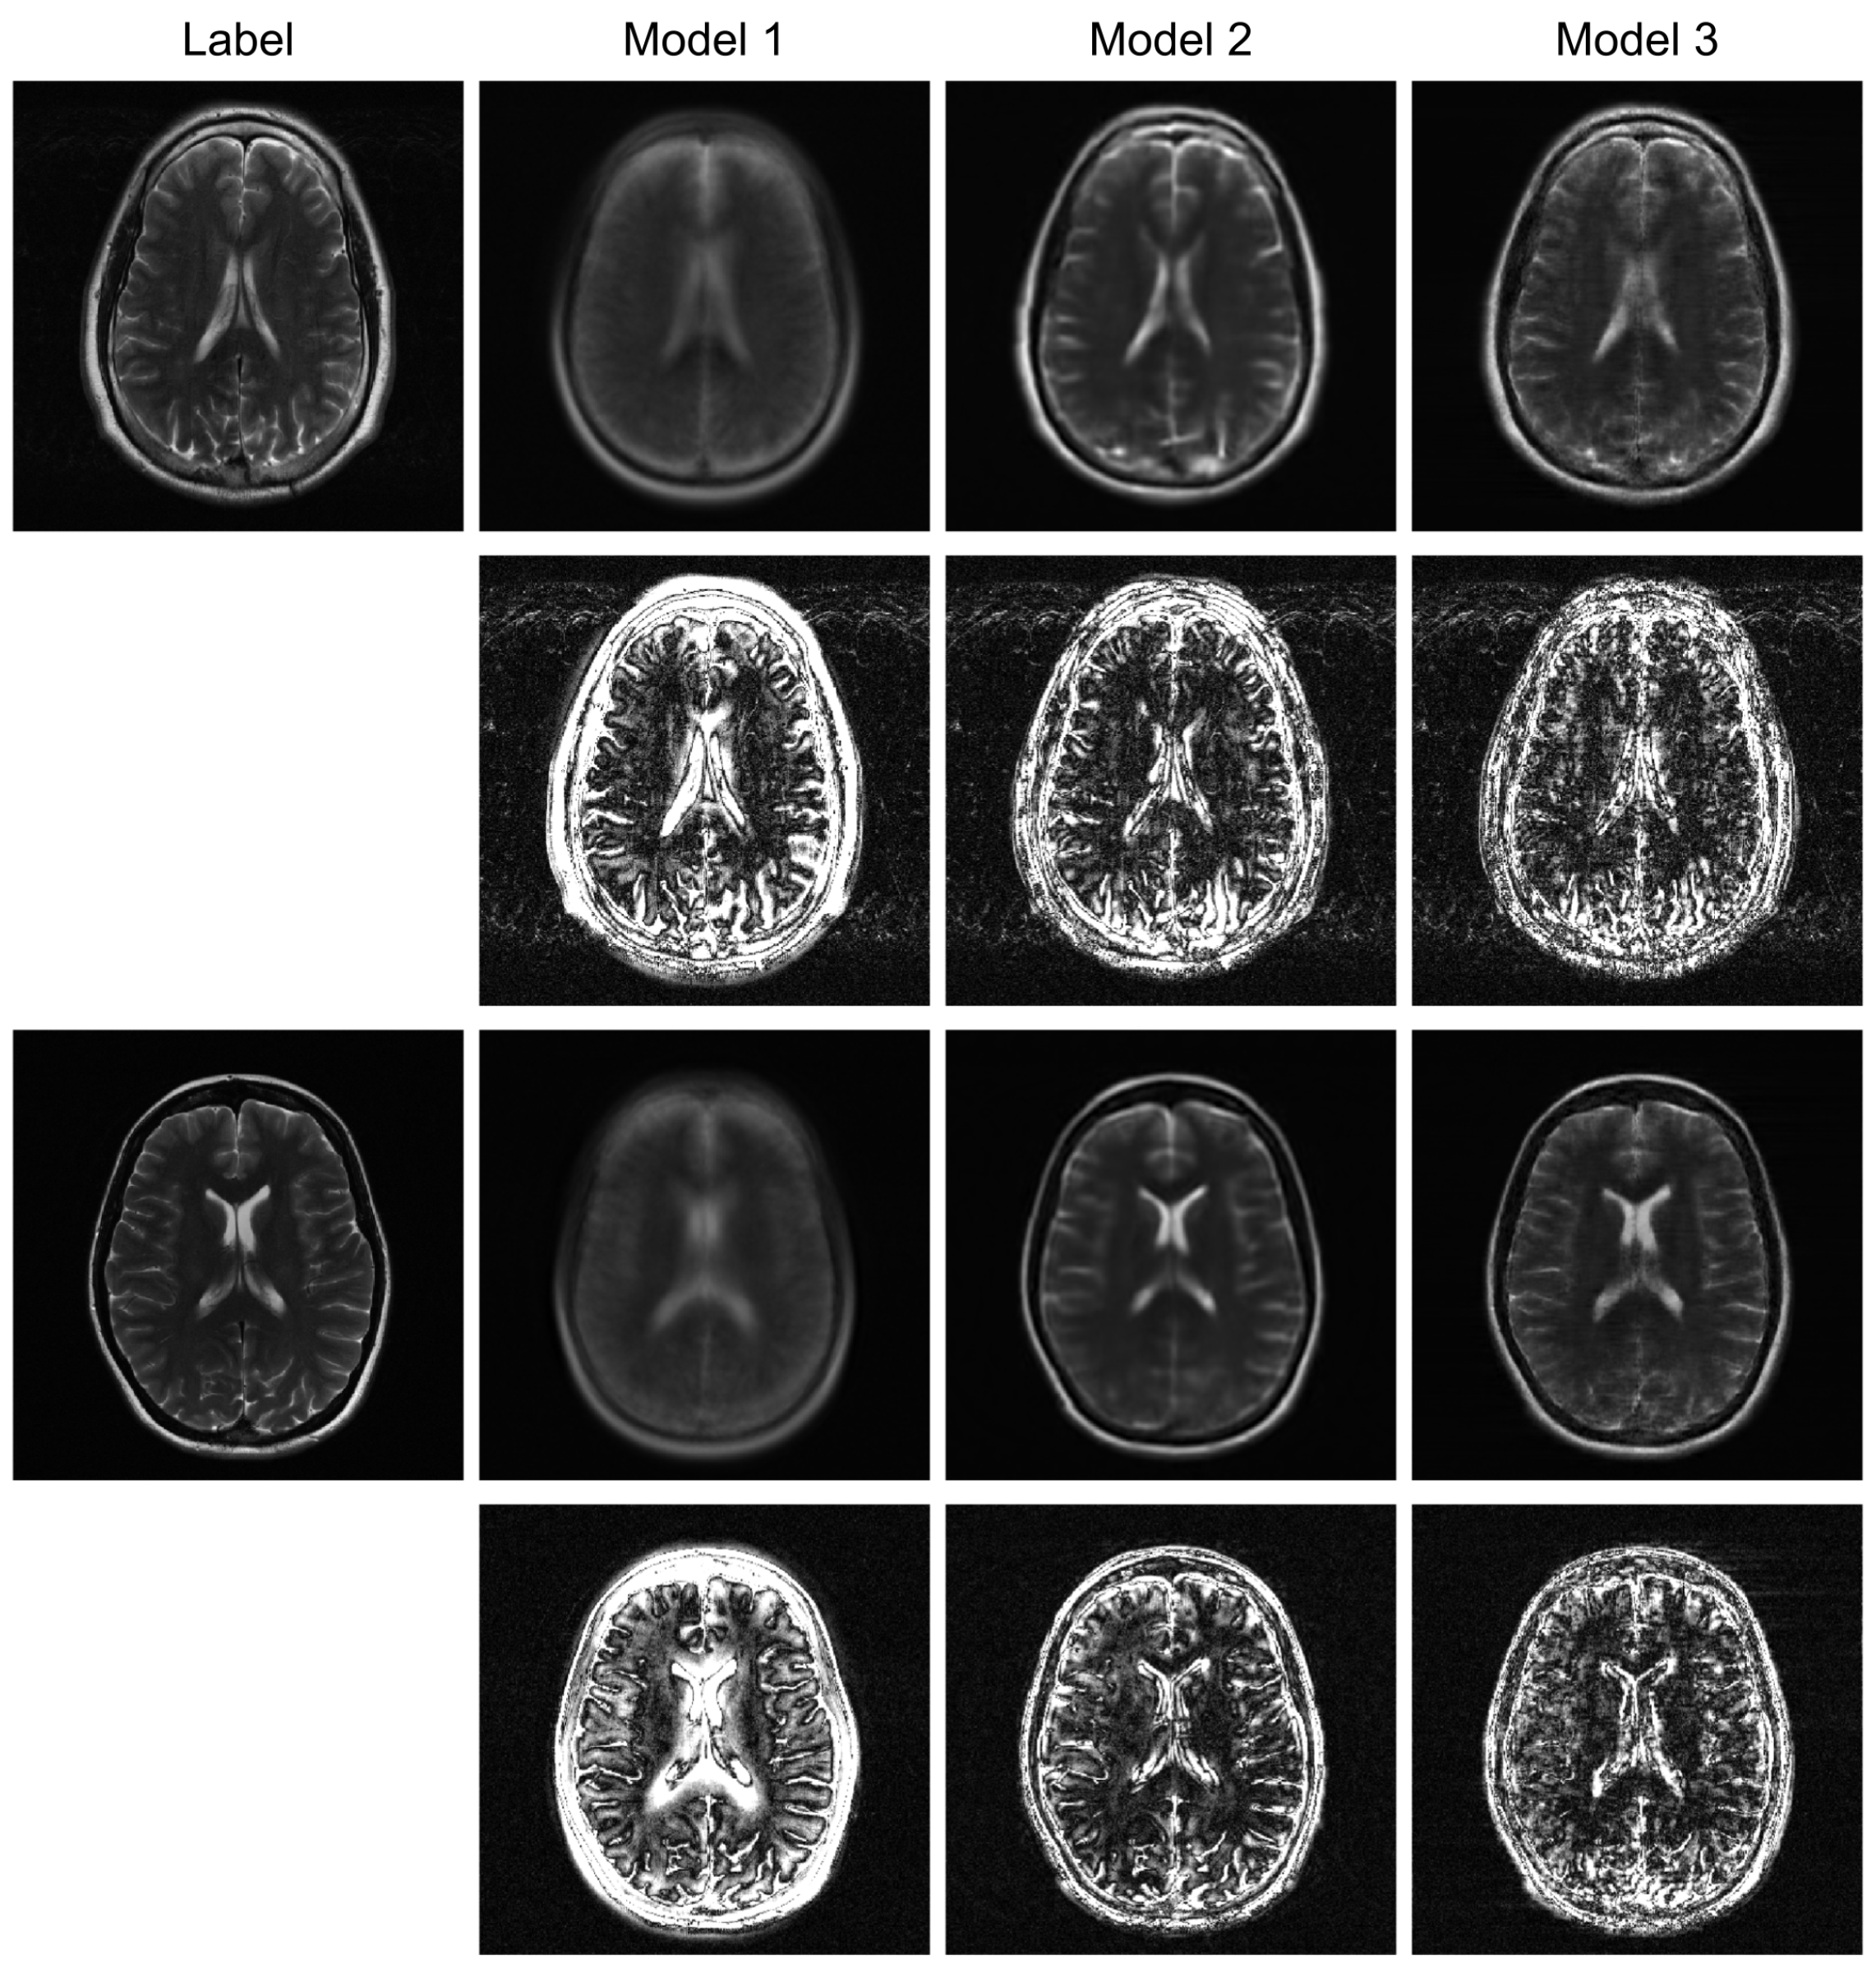

To further evaluate the robustness of our proposed model, we conducted additional experiments under higher acceleration factors (R = 8) and with different undersampling patterns (regular and random). For the random sampling scenarios, a new undersampling mask was randomly generated for each sample, which prevents the model from overfitting to a fixed pattern and enhances generalization. The qualitative results are presented in Figure 3, Figure 4 and Figure 5, and the corresponding quantitative analysis is summarized in Table 1. At a higher acceleration factor of R = 8 (Figure 4 and Figure 5), the performance gap between the models becomes more pronounced. While all models exhibit increased artifacts compared to R = 4, Model 3 consistently preserves anatomical structures more effectively than the other models, particularly in the more challenging random sampling scenario (Figure 5). The quantitative results in Table 1 align with the visual assessment. Across all tested scenarios—R4 random, R8 regular, and R8 random—Model 3 consistently achieves the lowest nMSE and the highest SSIM and VIF scores.

The comparison between Model 2 and Model 3 effectively serves as an ablation study, isolating the contribution of the BiRNN module. The significant performance improvement observed in Model 3, particularly under high acceleration (R = 8) and random sampling conditions (Table 2), underscores the critical role of processing k-space data directly. While the Transformer decoder in Model 2 can reconstruct global structures from the encoder’s latent features, it struggles with the complex, non-local aliasing artifacts inherent in undersampled data. The BiRNN module in Model 3 addresses this by interpreting k-space as sequential data, effectively capturing the structured correlations along the phase-encoding directions. This allows the model to disentangle aliasing patterns from true anatomical features before the final fusion step, resulting in superior artifact suppression and detail preservation, as visually confirmed in Figure 4 and Figure 5.

Furthermore, the model’s robustness against different sampling patterns demonstrates its generalization capabilities. The regular sampling pattern (Figure 5) produces coherent, line-like artifacts, whereas the random pattern (Figure 4 and Figure 6) generates more incoherent, noise-like artifacts. Model 3’s consistent high performance in both scenarios indicates that the hybrid architecture, which processes global image-domain context via the ViT and models frequency-domain sequential dependencies via BiRNNs, achieves high adaptability to varying artifact structures. This adaptability is a significant advantage over methods optimized for only a specific type of artifact texture.

Figure 4. Qualitative evaluation on R = 4 randomly undersampled data. This figure compares the reconstruction outcomes and amplified (10×) error maps for Model 1, Model 2, and the proposed Model 3.